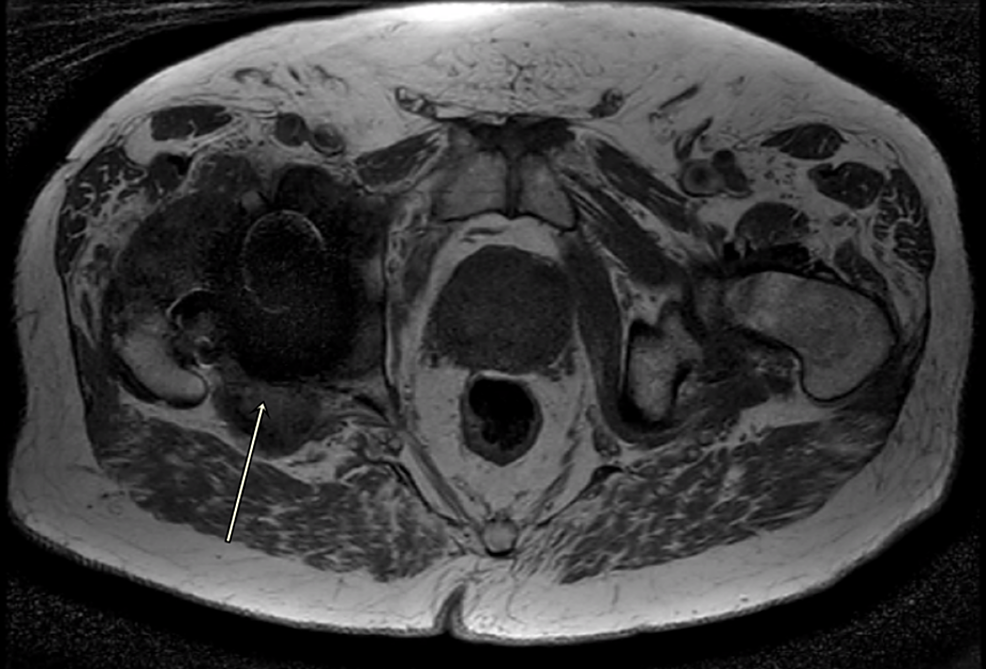

From www.cureus.com

Cureus A Case Report and Literature Review to Aid in the Management Trunnionosis Radiology Both total and resurfacing mom arthroplasty have been reported as associated with tribocorrosion or trunnionosis, which results from metal ion generation at the. It is defined as wear or corrosion at the trunnion, the. Reaction to metal is a spectrum of periprosthetic aseptic inflammation triggered by products of corrosion and metallic debris from. The imaging findings of periprosthetic soft tissue. Trunnionosis Radiology.